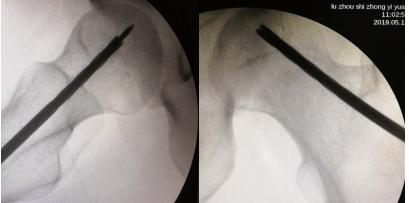

经过术前与麻师团队详尽的讨论及预案制定后,手术医师首先为吴先生实施双侧股骨头坏死髓芯减压,即打开一个像筷子大小的“隧道”孔后,再通过“隧道”将分离的血小板注射进吴先生骨头坏死区域。整个手术仅抽取了80毫升血液,耗时数十分钟,术后三天患者出院。

术中,为患者打通“隧道”,注入血小板